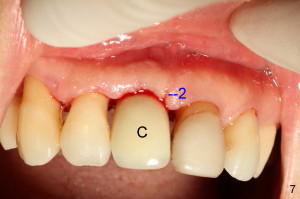

Fig.4 shows incision design for implant uncover (following osseous surgery in the upper right quadrant). The main incision is indicated by black line, lingual to the crest so that the buccal flap is more bulky. It is curved and festooned to create the future cosmetic buccal gingival margin. If the main incision is placed too lingual to expose the implant, one or two accessory incisions (red) can be made. After insertion of 4x6.5 mm non-shouldered abutment 3 mm post, PVS impression is taken. Fig.5 shows temporary crown in place (T) with two vertical mattress suture in the mesial and distal papillae. Two accessory incisions are approximated. Two weeks later, the temporary crown is removed. The accessory incision #1 has healed, while #2 is healing (Fig.6). The temporary crown helps form a nice socket around the abutment (A). Fig.7 shows the gingiva around the crown (to be cemented) with healing incision #2. Five months after crown cementation, the gingiva looks healthy.